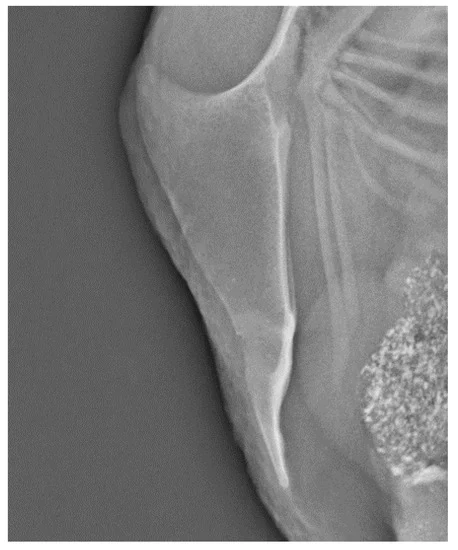

这是多处骨折的龙骨( 63 周龄):

根据哥本哈根大学的一项研究[1],超过 85%的丹麦产蛋鸡患有龙骨(胸骨)骨折 。这些骨折并非源于外部撞击,而是源于“内部负荷”。

巨大的鸡蛋在输卵管子宫部钙化变硬后,就像一块坚硬的石头占据了腹腔。随着母鸡的每一次呼吸和运动,这块“石头”从内部不断挤压脆弱的龙骨,最终导致骨骼断裂。要知道,产蛋鸡为了形成蛋壳,必须从自己的骨骼中抽取大量钙质,这本就导致了严重的骨质疏松 。